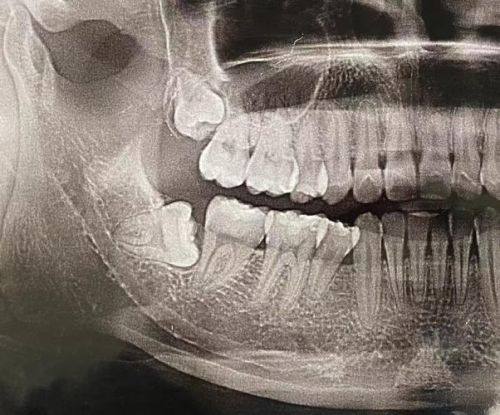

另外,如果智齿拔除过程比较复杂,创口比较大,修复时间也会更长。比如阻生智齿,拔除难度大,创口大,可能需要更久的时间才能喝酒。所以,不能一概而论,要根据自己的实际情况来判断。